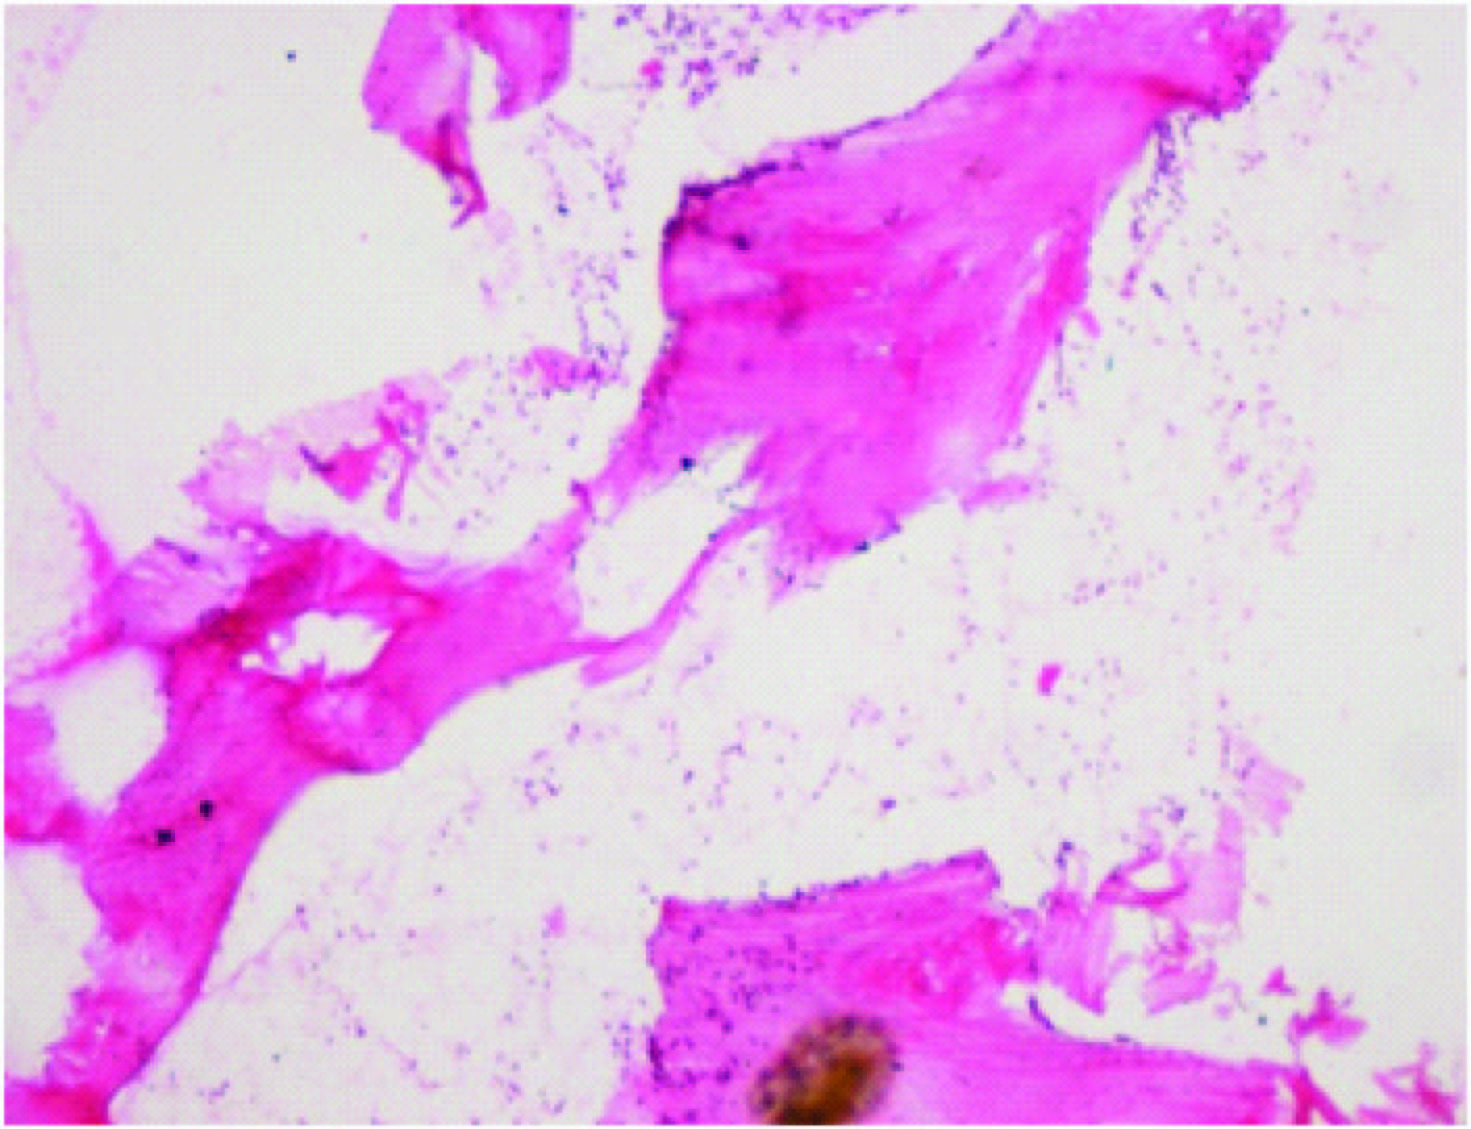

Bone marrow trephine biopsy section showing hypercellular marrow. (H&E, X200)